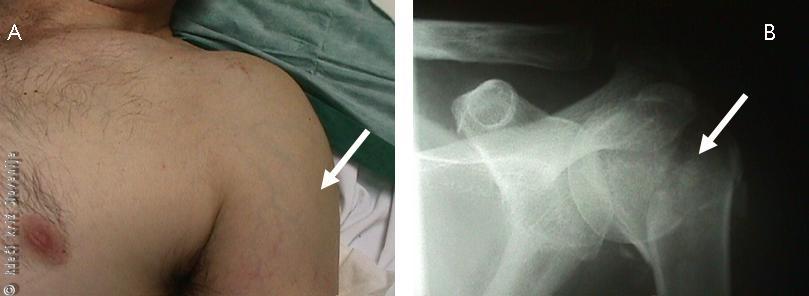

Slika 4

A – Zlom vratu nadlahtnice z oteklino in spremenjeno obliko.

B – Zlom zanesljivo potrdimo z rentgensko sliko.